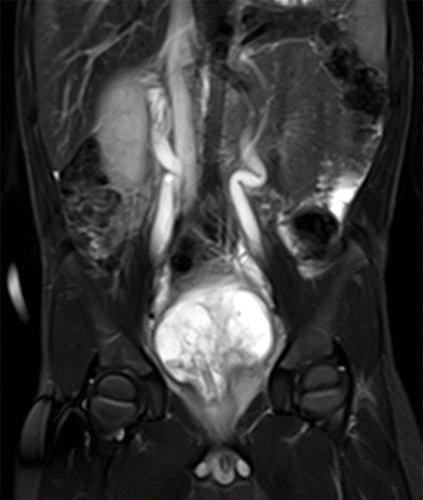

Born with it and associated with bilateral Wilms

A

Nephroblastomatosis

Picture of nephroblstomatosis + Wilms

Screening ultrasound every 3 months until patient turn 8